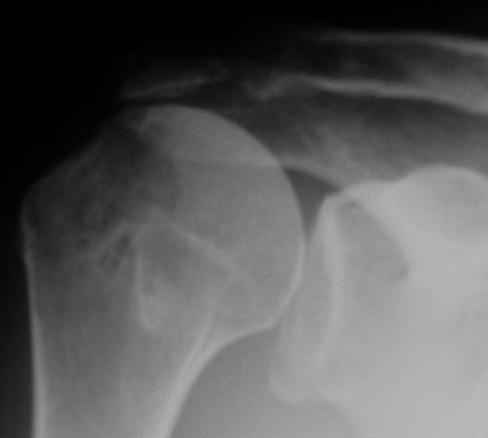

Физический активный мужчина 50 лет в мае 2009 года был оперирован на правом плечевом суставе. Выполнялся открытый шов надостной мышцы и субакромиальная декомпрессия по поводу ее частичного разрыва и импиджмент синдрома III степени. Послеоперационный период протекал без осложнений. Гипсовая иммобилизация в положении отведения плеча до 45 градусов в течение 6 недель.В последующем, несмотря на активные занатия ЛФК, сформировалась приводяще-внутриротационная контрактура оперированного сустава (отведение до 80 градусов, наружная ротация до 15 градусов. Болевого синдрома нет, при пассивном отведении плеча создается впечатление "механического" препятствия движению.На контрольных рентгенограммах складывается впечатление о сформировавшемсся верхнем подвивихе головки правой плечевой кости, как о причине контрактуры. Хотелось бы услышать мнение коллег о такттике дальнейшего лечения.

К сожалению, более подробной информации из выписного эпикриза почерпнуть не удалось (больной был оперирован, наблюдался и проходил реабилитацию в другом лечебном учреждении. Полностью согласен, что высокое стояние головки плеча, вероятнее всего, свидетельствует о неадекватном восстановлении ротаторной манжеты, к счастью пока без выраженных рентгенпризнаков ротаторной артропатии.